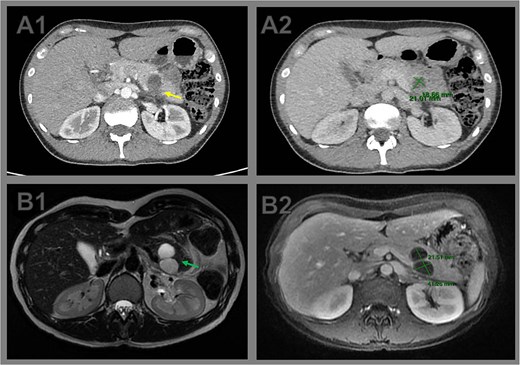

Two weeks later, the patient developed severe abdominal pain requiring hospitalization. Magnetic resonance imaging (MRI) demonstrated enlargement of the bilobulated cystic lesion to 4.0 × 2.0 cm, with internal septations and thickened contents, consistent with rupture. Associated findings included peripancreatic fat stranding and posterior pararenal fascial thickening. The leading diagnosis was an MCN with partial rupture and secondary pancreatitis; an inflammatory pseudocyst was considered less likely (Fig. 1).

Comparative cross-sectional imaging illustrating progressive growth and signs of rupture in a pancreatic cystic neoplasm. (A1) Axial contrast-enhanced CT image at initial evaluation showing a unilocular cystic lesion at the body–tail junction of the pancreas. The posterior wall appears indistinct (arrow), raising suspicion of partial cyst rupture. (A2) CT measurement of the cystic lesion, with dimensions of 2.1 × 1.8 cm. (B1) Axial T2-weighted MRI performed 2 weeks later reveals a bilobulated cystic lesion in the pancreatic tail, with internal septations (arrow). (B2) Axial T1-weighted MRI shows interval growth of the lesion to 4.0 × 2.1 cm, confirming enlargement and supporting the diagnosis of cyst rupture with associated inflammatory changes.